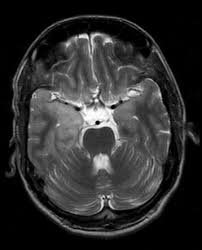

Clinico Radiological Spectrum Of Bilateral Temporal Lobe Hyperintensity A Retrospective Review Abstract Europe Pmc

Clinico Radiological Spectrum Of Bilateral Temporal Lobe Hyperintensity A Retrospective Review Abstract Europe Pmc from europepmc.org

Herpes simplex (hsv) encephalitis is the most common cause of fatal sporadic fulminant necrotising viral encephalitis and has characteristic imaging findings. The differential diagnoses include limbic encephalitis (paraneoplastic), gliomatosis cerebri, and status epilepticus. The basal ganglia are usually spared. Note the high signal in the caudate heads and putamen on flair. Bilateral temporal lobe t2 hyperintensity refers to hyperintense signal involving the temporal lobes on t2 weighted and flair imaging. It is reasonable to obtain an mri when patients are asymptomatic to ensure that no other abnormality is present which may be causing a recurrent chemical meningitis (e.g. For a general discussion, and for links to other system specific manifestations, please refer to the article on hydatid disease. Radiopaedia is free thanks to our supporters and advertisers.

Axial t2 prominent swelling, increase t2 signal involving the left temporal lobe and insular cortex. It is estimated to occur in ~2% of pati. Become a gold supporter and see no ads. This patient went on to have hsv encephalitis proven on csf pcr. A brain biopsy was performed and the histology was consistent with encephalitis. The differential diagnoses include limbic encephalitis (paraneoplastic), gliomatosis cerebri, and status epilepticus. Multilocularis.the larval stage is the cause of hydatid disease in humans 1. It is usually bilateral but asymmetrical. Spinal hydatid disease is an uncommon manifestation of hydatid disease, caused by the larval stage of echinococcus granulosus, or less commonly e. Limbic encephalitis, mca ischaemia, tumours, effects of seizures) hyperintense t2 signal in the medial temporal lobes, inferior frontal lobes and insula basal ganglia are usually spared It is reasonable to obtain an mri when patients are asymptomatic to ensure that no other abnormality is present which may be causing a recurrent chemical meningitis (e.g. 10 public playlist includes this case Pcr was repeated on the biopsy specimen and was positive for hsv.